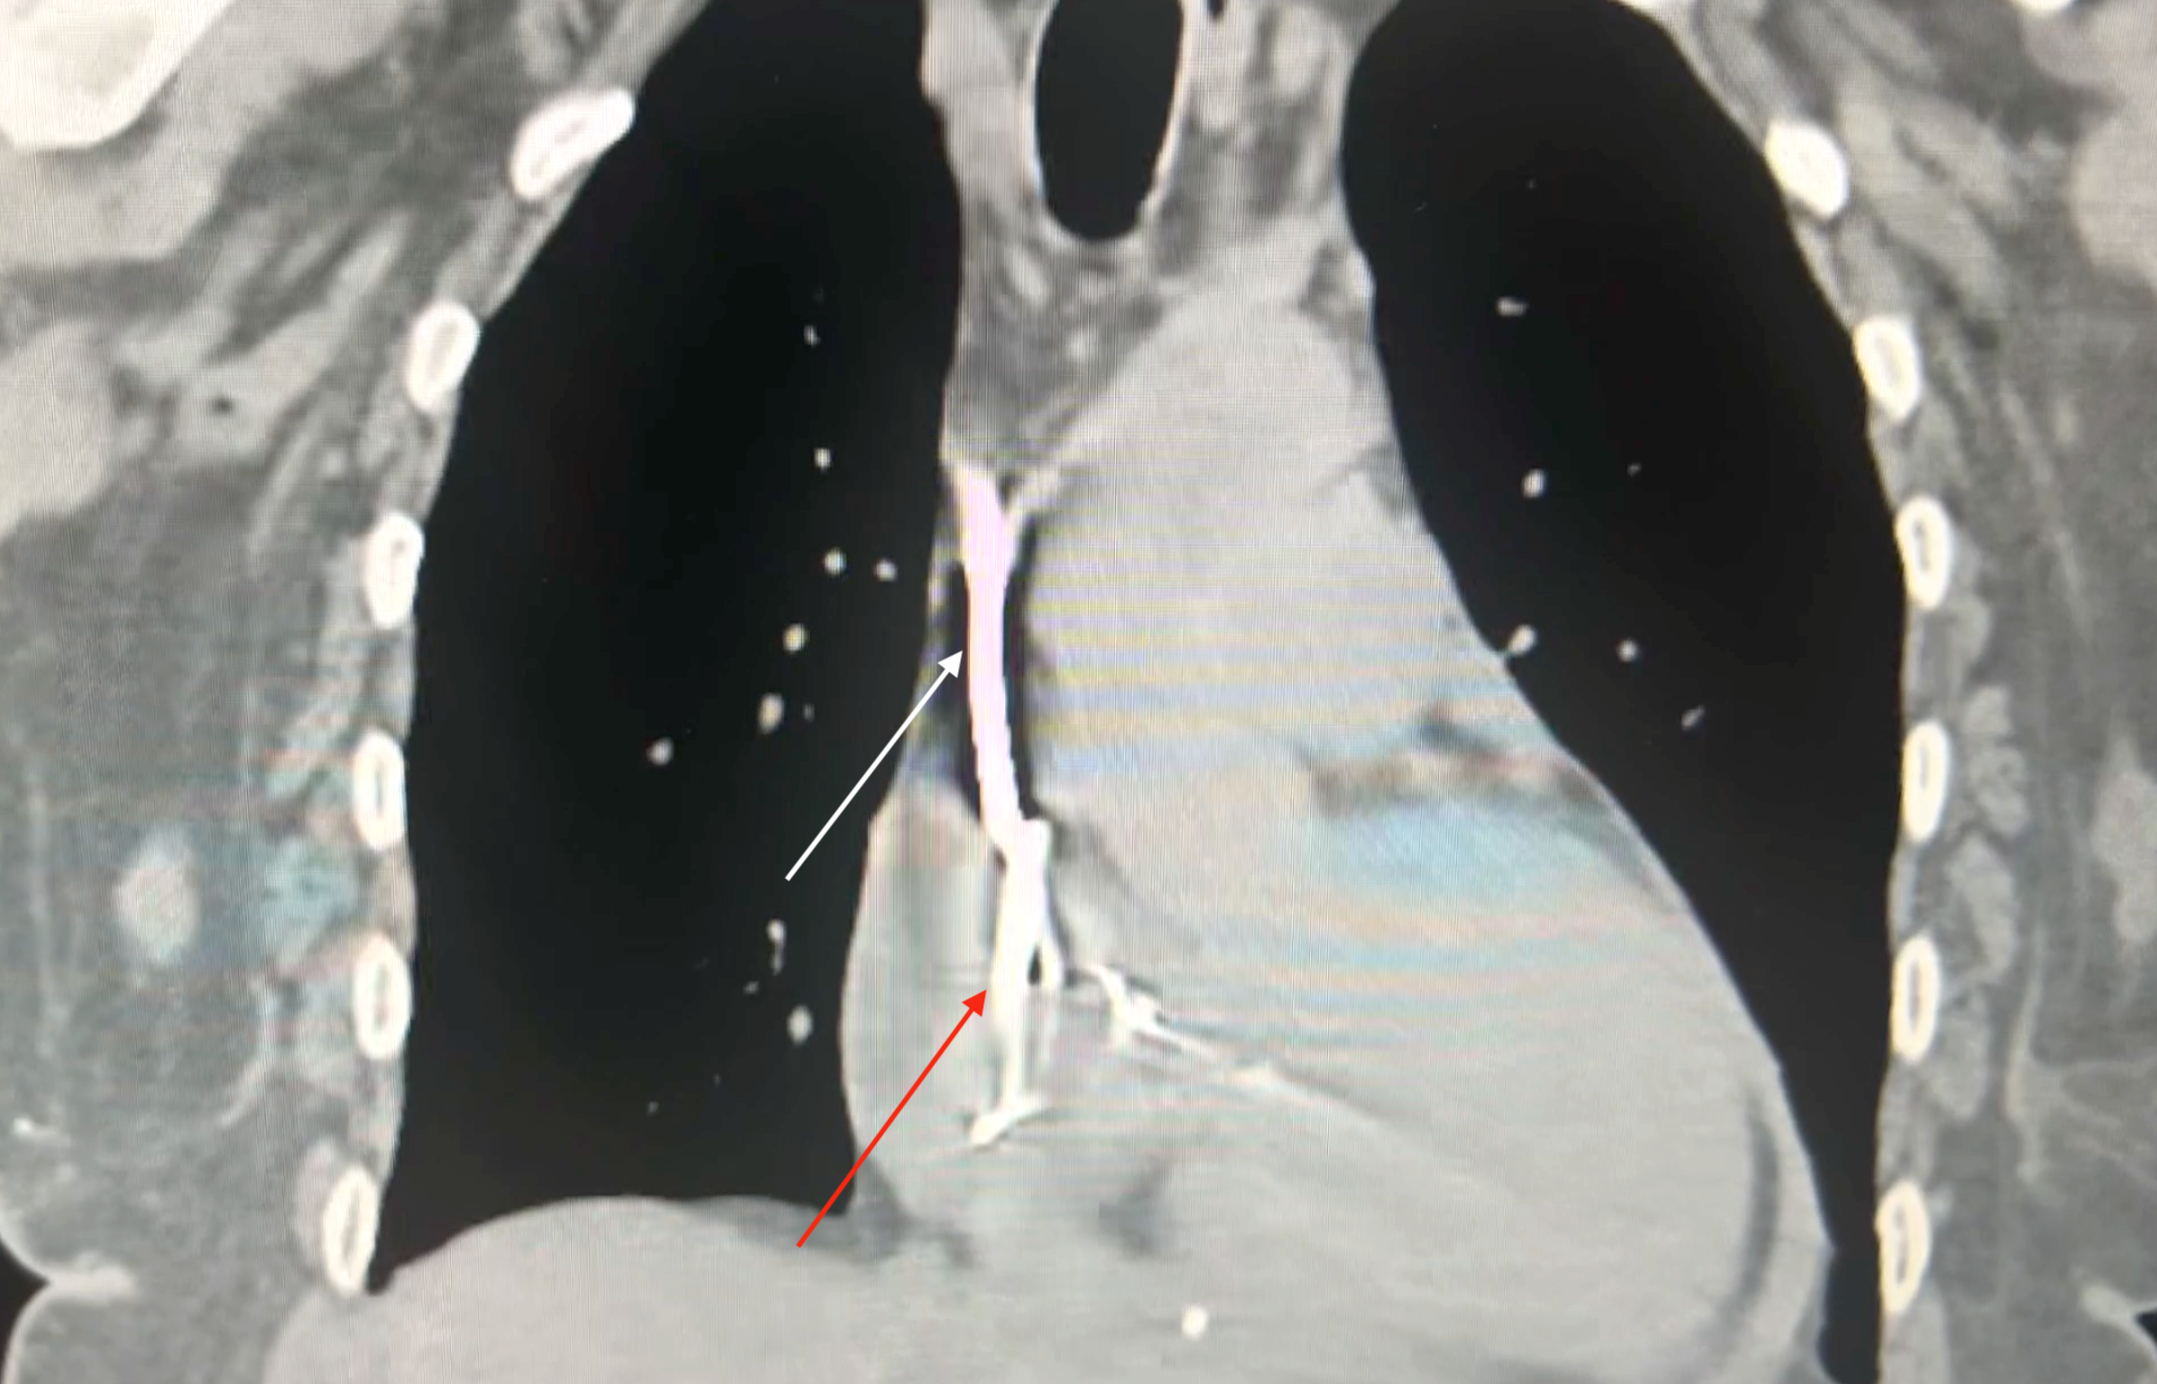

Case: A 61-year-old woman with heart failure with reduced ejection fraction (EF 25%), end-stage renal disease on hemodialysis, and a history of breast cancer presented with a malfunctioning hemodialysis catheter. After unsuccessful local alteplase, interventional radiology performed a left femoral hemodialysis catheter exchange. Within one hour post-procedure, the patient developed syncope, hypotension (60/40 mmHg), tachycardia (120 bpm), and reported chest discomfort, weakness, and lightheadedness. Bedside electrocardiogram showed sinus tachycardia with electrical alternans. Emergent echocardiography revealed a moderate circumferential pericardial effusion with right atrial systolic and right ventricular diastolic collapse, distended inferior vena cava, and marked respirophasic variation of atrioventricular inflow velocities, consistent with cardiac tamponade. Chest radiography suggested the catheter tip abutting the right atrial free wall. The delayed perforation was likely due to catheter migration and erosion. Despite aggressive fluid resuscitation and norepinephrine infusion (up to 35 mcg/hr), the patient remained unstable. Bedside pericardiocentesis drained approximately 700 mL of blood, resulting in rapid hemodynamic improvement and discontinuation of vasopressors within one hour. Computed tomography confirmed the catheter tip’s proximity to the right atrial wall. Cardiothoracic surgery determined that surgical intervention was unnecessary as the perforation had sealed spontaneously.